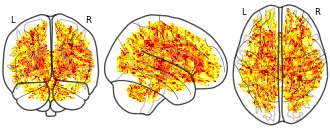

EmailClick to copy linkLink copied Cite(2020). Exploring white matter microstructure and the impact of antipsychotics in adolescent-onset psychosis: FA map, contrast patients > controls (unthresholded t map) [Dataset]. http://identifiers.org/neurovault.image:387082niftiAvailable download formatsUnique identifierhttps://identifiers.org/neurovault.image:387082Dataset updatedMay 15, 2020License

Cite(2020). Exploring white matter microstructure and the impact of antipsychotics in adolescent-onset psychosis: FA map, contrast patients > controls (unthresholded t map) [Dataset]. http://identifiers.org/neurovault.image:387082niftiAvailable download formatsUnique identifierhttps://identifiers.org/neurovault.image:387082Dataset updatedMay 15, 2020LicenseCC0 1.0 Universal Public Domain Dedicationhttps://creativecommons.org/publicdomain/zero/1.0/

License information was derived automaticallyDescriptionFor contrasting case-control differences, we run voxel-wise statistics for FA using a nonparametric permutation-based approach (FSL, Randomise, 5000 permutations). Age and sex were entered as covariates. All covariates were demeaned. The map shows uncorrected test statistic (see https://fsl.fmrib.ox.ac.uk/fsl/fslwiki/Randomise/UserGuide).

Collection description

Unthresholded t- and corrected p-maps of the scalar diffusion measures fractional anistropy (FA), axial diffusivity (AD) and radial diffusivity (RD), contrasting adolescent patients with early onset psychosis versus adolescent healthy controls (i.e. contrast 1: patients >controls; contrast 2: patients > controls, covariates: age and sex).

Preprint: https://www.biorxiv.org/content/10.1101/721225v2